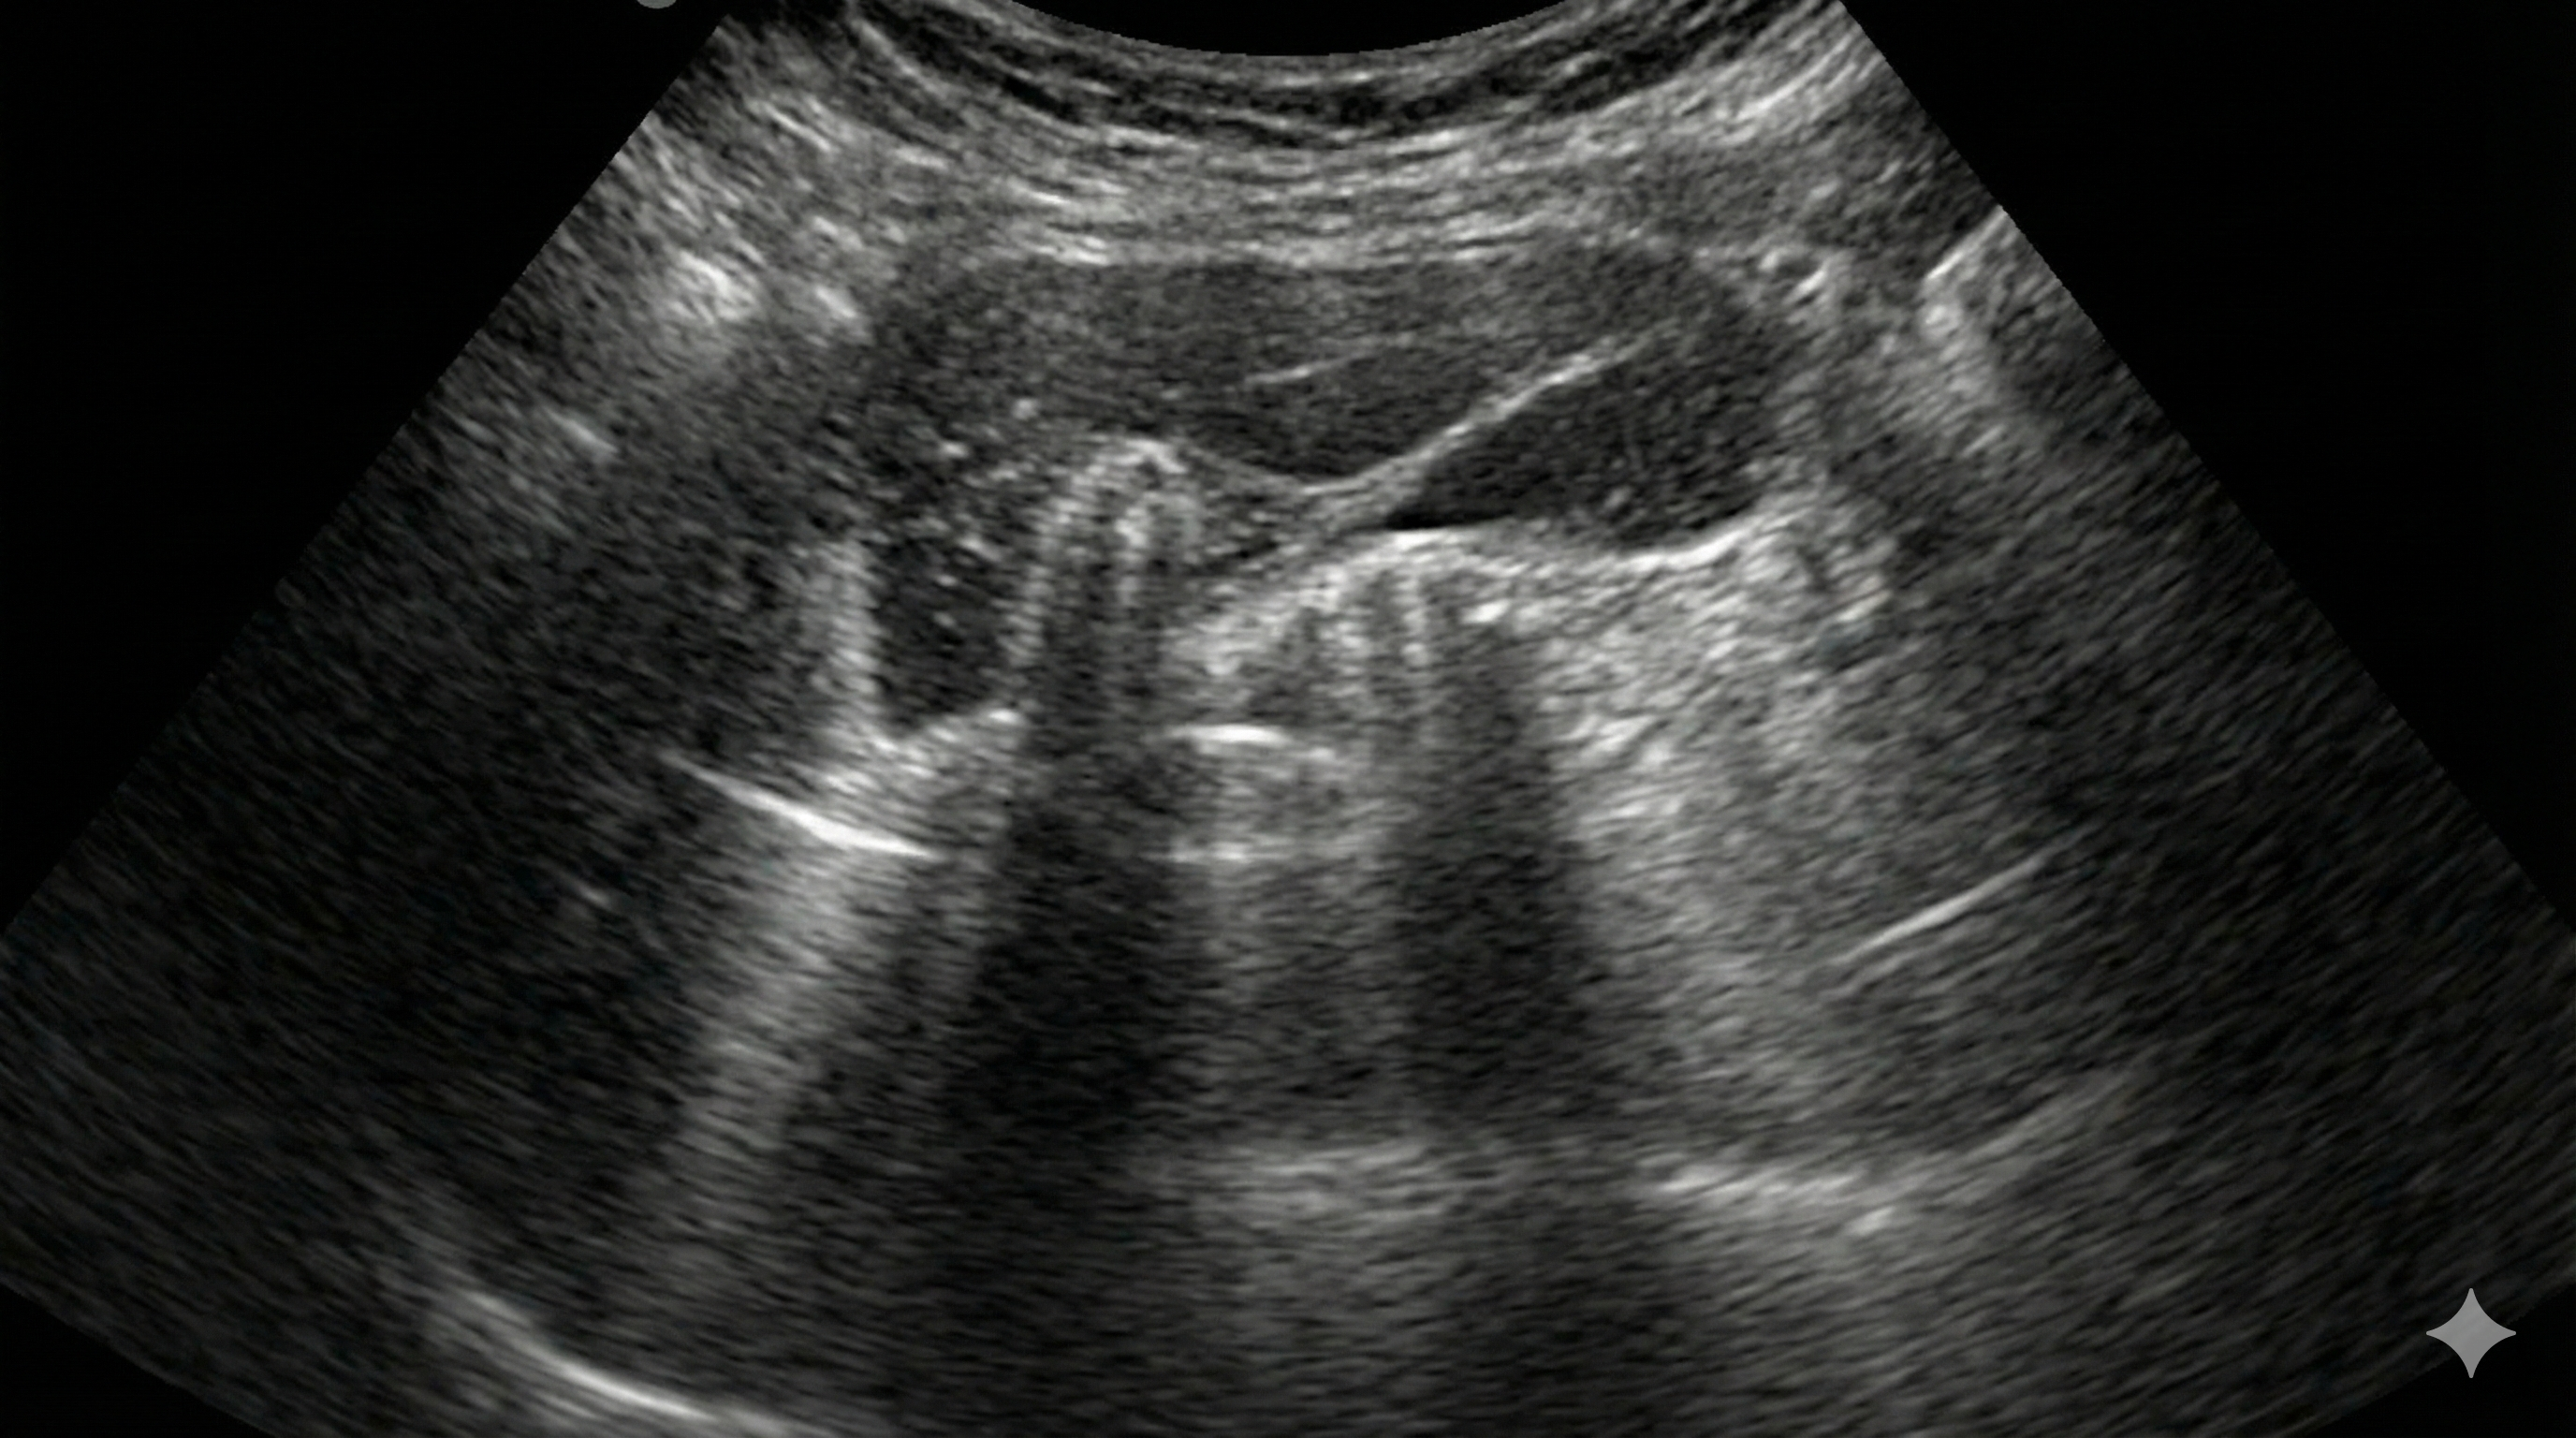

Figure 1 Hallazgos ecográficos típicos en enfermedades pulmonares frecuentes.

| Patología | Hallazgo típico en LUS | Citaciones |

|---|---|---|

| Edema cardiogénico | Líneas B difusas, perfil B | 1 |

| Neumonía | Consolidación + broncograma, B focales | 2 |

| Neumotórax | Ausencia de deslizamiento, “lung point” | 3 |

| Derrame pleural | Quad + sinusoid sign | 4 |